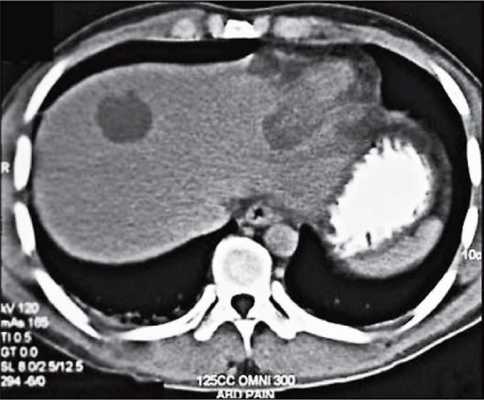

Абсцессы печени

Абсцессы печени могут быть пиогенными* или обусловленными амебиазом (инфекцией, поражающей толстую кишку с образованиями язв на ее оболочке) и микозом (грибковой инфекцией). При абсцессе печени пациент испытывает боли в правом боку, а в некоторых случаях болевые ощущения сопровождаются лихорадкой.

Абсцессы печени проходят три стадии развития, и МР-картина варьируется в зависимости от них. В первые 10 дней возникает некроз с мелкими участками разжижения. К 10-15-му дню некротический детрит рассасывается (на его месте теперь преобладает жидкость). После 15 дней еще сохраняется небольшое количество детрита, окруженного толстой фиброзной стенкой. МРТ дает возможность визуализировать заболевание на всех этапах.

Абсцесс печени и МРТ

Магнитно-резонансная томография позволяет идентифицировать абсцесс, локализовать его и определить размеры. Специальный режим диффузионно-взвешенных изображений придает абсцессу яркий МР-сигнал, а на ИКД-картах* - низкий.

Кроме того, МРТ позволяет оценивать динамику процесса в ходе лечения, ведь даже при своевременной терапии для излечения больших абсцессов могут потребоваться месяцы.

Нередко абсцессы сопровождаются тромбозом печеночных вен или воспалением желчного пузыря. По этой причине при абсцессе печени важно исключить его взаимодействие с желчными путями. Комплексное исследование органов брюшной полости и забрюшинного пространства позволит лечащему врачу оценить состояние не только печени, но и окружающих тканей.